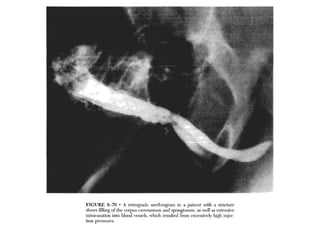

This document discusses the considerations and precautions for retrograde urethrography (RGU), noting that local anesthetic may cause issues such as mucosal edema. It highlights the need for antibiotic coverage due to potential complications like extravasation during contrast injection, and touches upon the role of cystography in pelvic fractures, indicating it can often be safely omitted. Additionally, it reports on complications related to urinary tract infections and reactions to contrast media, offering recommendations for patient management.